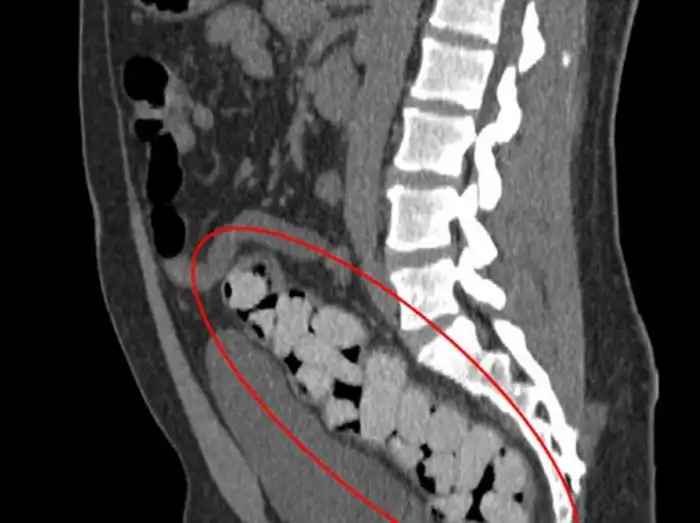

20 контейнеров с наркотиками в толстой кишке

Эти цветные пакетики наркотиков находятся в толстой кишке

Наркотики в толстой кишке